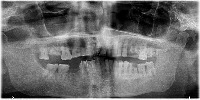

Dental Treatment Planning: The Dentistry computer vision model can be used by dentists and orthodontists for analyzing dental X-rays to identify teeth numbers and conditions like implant, root canal, or crown. By having automatic classification, it will improve the efficiency and accuracy of the treatment planning process.

Dental Education and Training: The model can be utilized as a learning tool for dental students, helping them to familiarize themselves with tooth numbering, implants, crowns, and root canals. This could be implemented in virtual classrooms or integrated into educational mobile applications.

Dental Insurance Claim Processing: The Dentistry computer vision model can be employed by insurance companies to automatically process dental claims. The model can identify the specific treatments or procedures (such as root canals or implants) from the dental X-ray images, leading to faster and more accurate claim processing.

Dental Record Management: Clinics and hospitals can use the Dentistry model to streamline their dental patients' record management by automatically categorizing X-ray images based on tooth number and treatment type. This will help in better organization of patient records and ease of access for future reference.

Dental Research and Analytics: The model can be valuable for dental researchers in the field of oral health analytics. By analyzing large datasets of dental X-ray images, the model can help identify patterns and trends for different treatments and tooth conditions, providing valuable insights for better oral care and health.